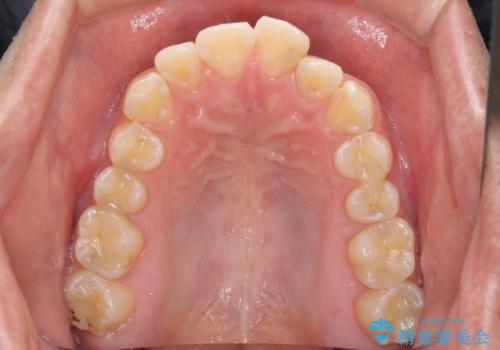

ディープバイトと叢生を解消 インビザライン矯正

- 前歯のデコボコを強い咬みしめを気にして来院された患者様です。

インビザラインを用いて、前歯の叢生を解消するとともに、ディープバイトを改善していくこととしました。

ディープバイトが改善されたことで、顎への負担が軽減され、更には上顎前歯の突出感も改善することができました。